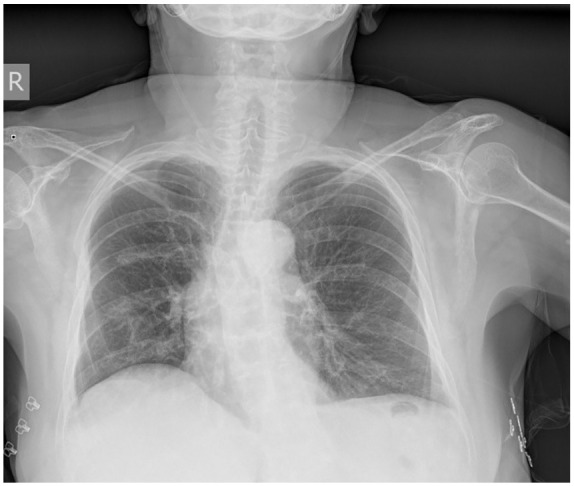

免疫相关神经肌肉疾病是用于治疗癌症的免疫检查点抑制剂(ICIs)罕见且可能危及生命的不良事件。他们往往有一个慢性过程,通常导致永久停止免疫治疗。我们提出一个病例的派姆单抗诱导重症肌无力,只涉及隔膜。患者是一名71岁女性,有IV期肺腺癌病史,在一线化疗免疫治疗完全缓解后,正在接受培美曲塞和派姆单抗的维持治疗。她自上月起主诉直呼,因低氧性呼吸衰竭入院。放射学显示肺体积减小,双肺下野无电区。随后的支气管镜检查排除了感染和癌症复发。肺功能检查显示一种混合性疾病,最大吸气压力严重降低,仰卧位与原位位相比肺活量大幅下降。横膈膜超声检查证实双侧横膈膜功能障碍,患者在睡眠中开始无创通气(NIV),症状得到缓解。神经系统检查未发现其他肌肉受累。重症肌无力综合征的实验室检测显示抗乙酰胆碱受体抗体滴度升高,这证实了重症肌无力的诊断。患者随后接受皮质类固醇、吡哆斯的明和静脉注射免疫球蛋白治疗,并逐渐能够停止补充氧气。在随访中,她的胸片和肺活量有所改善,但她继续使用NIV睡觉。停用了派姆单抗,9个月后,她仍然没有癌症。使用免疫疗法治疗癌症患者的临床医生应该意识到这种罕见的并发症,并在ICI治疗过程中及时调查任何一例矫直,以提供专门的管理。

Immune-related neuromuscular disorders are rare and potentially life-threatening adverse events of immune checkpoint inhibitors (ICIs) used in the treatment of cancer. They tend to have a chronic course that usually leads to the permanent discontinuation of immunotherapy. We present a case of pembrolizumab-induced myasthenia gravis that only involved the diaphragm. The patient is a 71-year-old female with a history of stage IV lung adenocarcinoma under maintenance therapy with pemetrexed and pembrolizumab after a complete response to first-line chemo-immunotherapy. She complained of orthopnea since the previous month and was admitted due to hypoxemic respiratory failure. Radiology showed decreased lung volumes and atelectatic areas in both lower lung fields. A subsequent bronchoscopy ruled out infection and cancer recurrence. Pulmonary function tests revealed a mixed disorder with a severe reduction in maximal inspiratory pressure and a large drop in vital capacity in the supine versus the sited position. Ultrasonography of the diaphragm confirmed bilateral diaphragmatic dysfunction, and the patient was initiated on non-invasive ventilation (NIV) during sleep, which led to symptom relief. A neurological physical examination did not reveal any other muscle involvement. Laboratory tests for myasthenic syndromes showed an elevated titer of the anti-acetylcholine receptor antibody, which confirmed the diagnosis of myasthenia gravis. The patient was subsequently treated with corticosteroids, pyridostigmine, and intravenous immunoglobulin and was gradually able to wean off supplemental oxygen. On follow-up, her chest X-ray and spirometry had improved, but she continued sleeping on NIV. Pembrolizumab was stopped, and she is still free of cancer after 9 months. Clinicians treating cancer patients with immunotherapy should be aware of this rare complication and perform timely investigations in any case of orthopnea in the course of ICI therapy to offer specialized management.